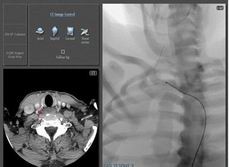

CT血管重建模塊(PROCEDURE)

CT血管重建模塊是可以將真實臨床患者的CT數(shù)據(jù)以DICOM數(shù)據(jù)格式傳輸?shù)窖芙槿肽M器(ANGIO Mentor)中,通過專業(yè)軟件PROcedure Rehearsal Studio的處理,可以重建臨床患者的心血管循環(huán)系統(tǒng),顯示患者的病變部位, 并在給患者手術(shù)之前在模擬器上進(jìn)行預(yù)手術(shù),構(gòu)建臨床手術(shù)計劃,減少病人的手術(shù)風(fēng)險。